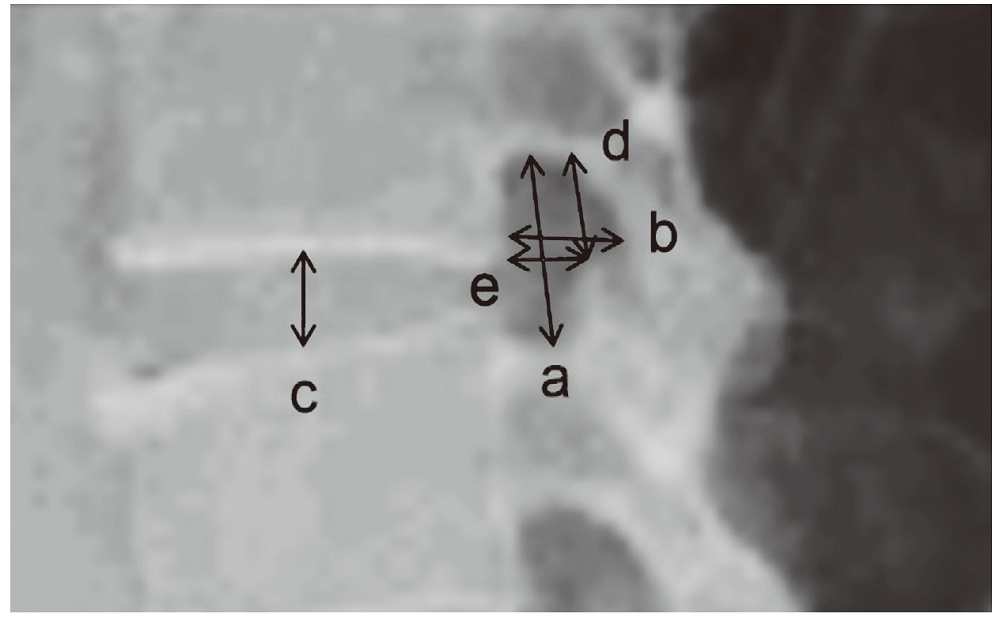

别业俊, 常晓涛, 武凯, 等. 国人腰椎椎间孔的骨性测量[J]. 中国中医骨伤科杂志, 2018, 26(12):5-8, 12

Yusof MI, Hassan MN, Abdullah MS. The relationship amongst intervertebral disc vertical diameter, lateral foramen diameter and nerve root impingement in lumbar vertebra[J]. Malaysian Orthopaedic Journal, 2018, 12(1):21-25

吴波, 赵庆豪, 周潇齐, 等. 腰椎间孔镜的应用解剖[J]. 中国临床解剖学杂志, 2017, 35(1):5-8

甄瑞鑫, 李玉波, 宋有鑫, 等. 椎下切迹的测量分析对经椎间孔入路的脊柱内镜技术的意义[J]. 实用骨科杂志, 2017, 23(10):879-883

Min JH, Kang SJ, Cho TH, et al. Morphometric analysis of the working zone for endoscopic lumbar discectomy[J]. Journal of Spinal Disorders & Techniques 2005, 18(2):132-135

Mirkovic SR, Schwartz DG, Glazier KD. Anatomic considerations in lumbar posterolateral percutaneous procedures[J]. Spine 1995, 20(18):1965-1971

Giles LG. A histological investigation of human lower lumbar intervertebral canal (foramen) dimensions[J]. J Manipulative Physiol Ther 1994, 17(1):4-14

Torun F, Dolgun H, Tuna H, et al. Morphometric analysis of the roots and neural foramina of the lumbar vertebrae[J]. Surgical Neurology 2006, 66(2):1-151